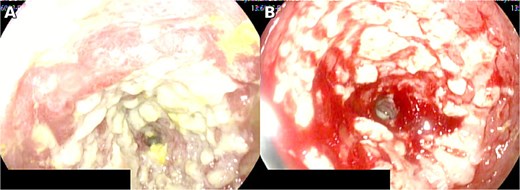

Laparotomy identified a stenotic, thickened segment ~50 cm distal to the ligament of Treitz (Fig. 2), and segmental resection with side-to-side anastomosis was performed. Histopathology and IHC confirmed CMV infection. Intravenous ganciclovir was initiated and continued for 7 days, with a favorable clinical course. At 1-week postoperative follow up, there were no signs of surgical site infection; the patient tolerated oral intake and had normal flatus and bowel movements. At 1-month and 3-month follow-up visits, she remained asymptomatic without new clinical abnormalities. Histopathological and IHC analyses confirmed CMV infection. Intravenous ganciclovir therapy was initiated with favorable outcomes [5, 6].

Clinical manifestations overlap with other causes of acute abdomen or obstruction; hence, 17 tissue diagnosis is required, demonstrating cytomegalic inclusions and positive IHC [2–4, 9]. In practice, IHC on tissue provides high specificity, whereas PCR may be complementary but can detect latent infection without proving tissue-invasive disease [4]. When the small bowel is involved, device-assisted enteroscopy enables targeted biopsies beyond the reach of standard endoscopy, thereby improving diagnostic yield [9]. In our patient, an extensive circumferential jejunal ulcer with stenosis, CT signs of obstruction, and lack of clinical improvement justified intestinal resection with anastomosis. Endoscopic patterns reported in immunocompetent individuals include irregular or circumferential ulcers with exudate and diffuse erythema, consistent with our findings [5]. In addition, imaging that demonstrates fixed transition points with proximal dilatation correlates with the need for operative management when clinical deterioration persists despite supportive care [6]. Concordance between imaging and intra-operative findings supported surgical planning, and histological confirmation guided antiviral therapy.